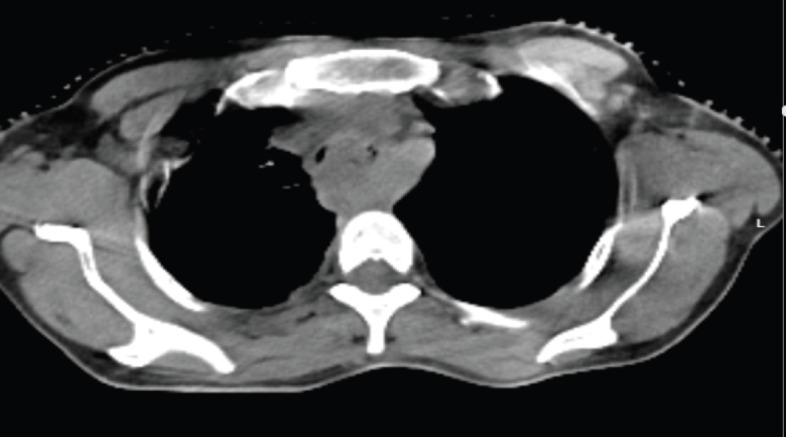

Abstract Image